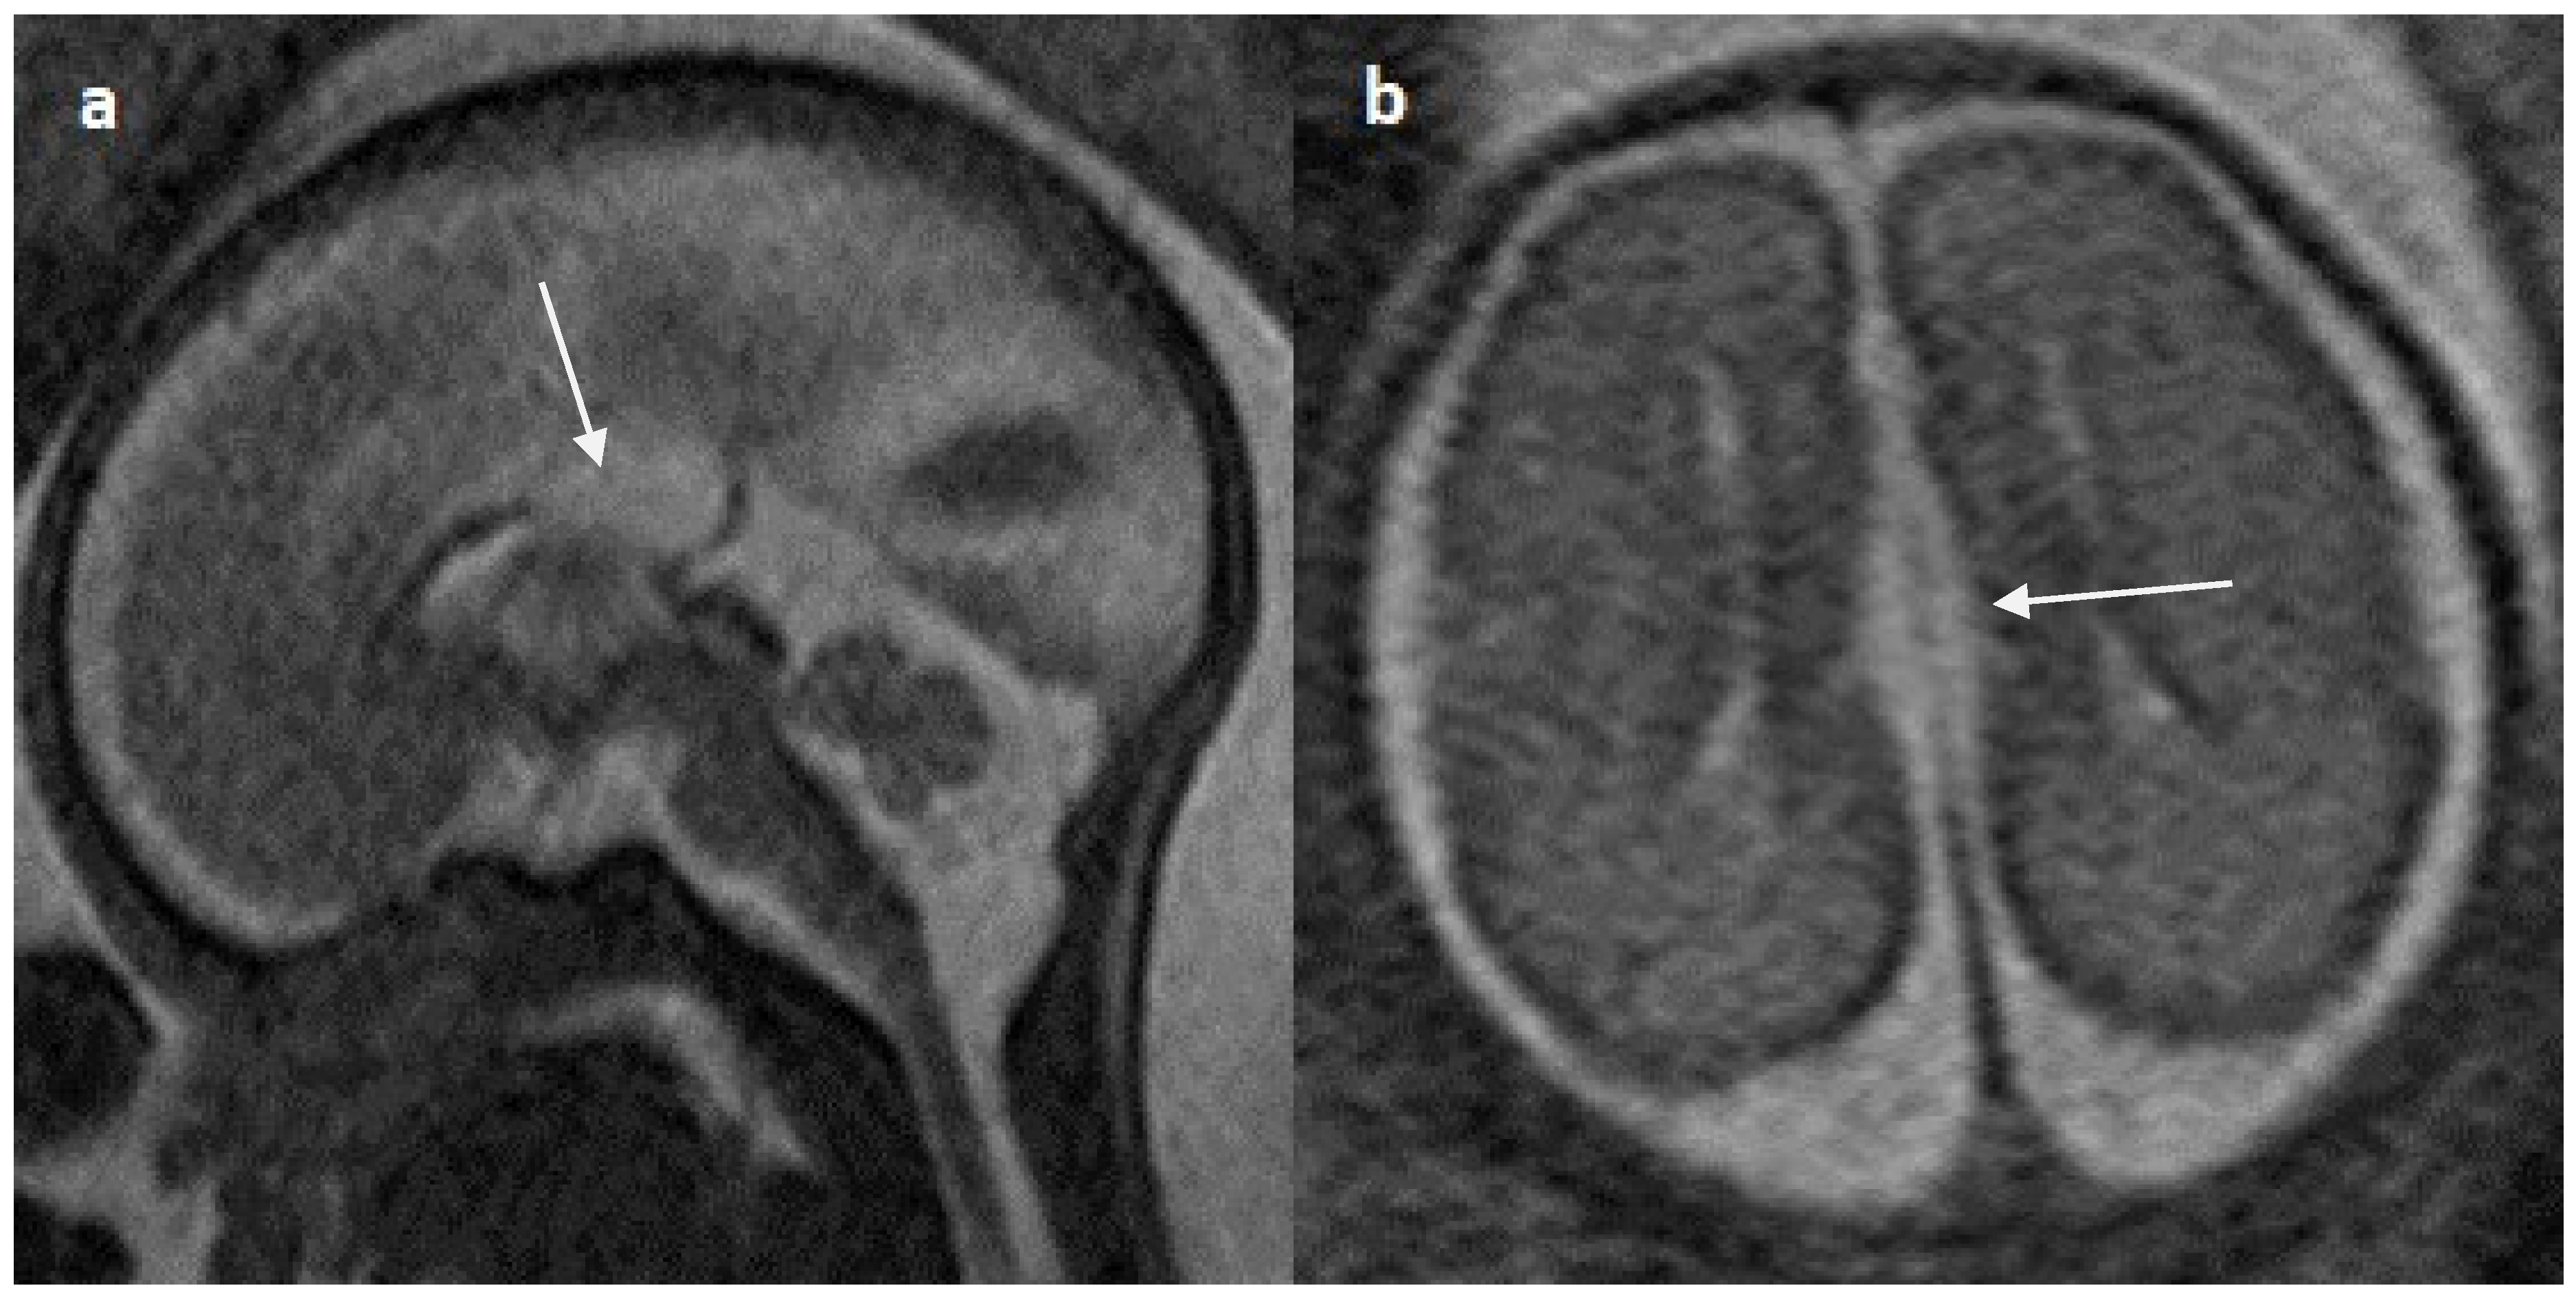

Colpocephaly is seen in 13/24 cases (54%) (Figure 5). Of them, 12 cases had complete agenesis, and one case had hypoplasia. Absent septum pellucidum is seen in 5/24 cases (20.8%) (Figure 6); 4 cases had complete agenesis, and one case had hypoplasia. Probst bundles are identified only in the isolated form of CCA and account for 3/19 cases (15.7%) of complete agenesis and 3/4 cases of the isolated form of CCA (Figure 7). Probst bundles are not seen in other subclasses of CCA. Ventriculomegaly is seen in 7/24 cases with an incidence rate of 0.29%, 5 cases had complete agenesis, and 1 case each had hypoplasia and hypoplasia with dysplasia.

Figure 5.

Fetal MRI images of a 31 gestational weeks aged fetus with complete agenesis of the corpus callosum. (a) A T2-weighted sequence image in sagittal plane shows that the corpus callosum is not visible (white arrow). (b) A T2-weighted sequence image in axial plane shows a “teardrop”-like dilation in the posterior horn of bilateral lateral ventricles suggestive of colpocephaly (white arrow) and absence of corpus callosum and septum pellucidum (red arrow) in the midline. (c) A T2-weighted axial image shows a small interhemispheric fluid collection/cyst in the midline. (arrow). No Probst bundles are observed.